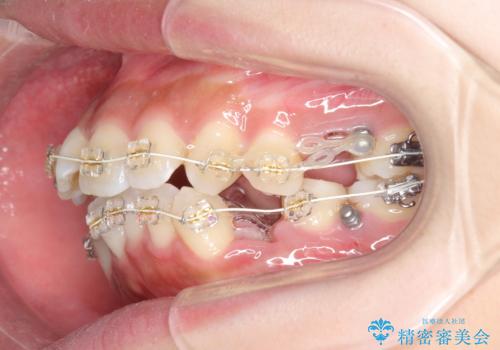

ガタつきと口元の改善 抜歯を伴うワイヤー矯正

- 唇の閉じづらさと、前歯のがたつきの改善を希望され来院されました。

抜歯を行わなくてもなんとか並べられる歯並びですが、唇の閉じづらさをしっかりと改善するため抜歯を伴うマルチブラケット矯正を行うこととしました。

前歯をしっかりと後方に引いたことで、唇は閉じやすくなり、仕上がりに満足いただくことができました。